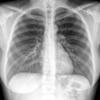

Normal PA Female

Date: 12/06/2014

Views: 5991